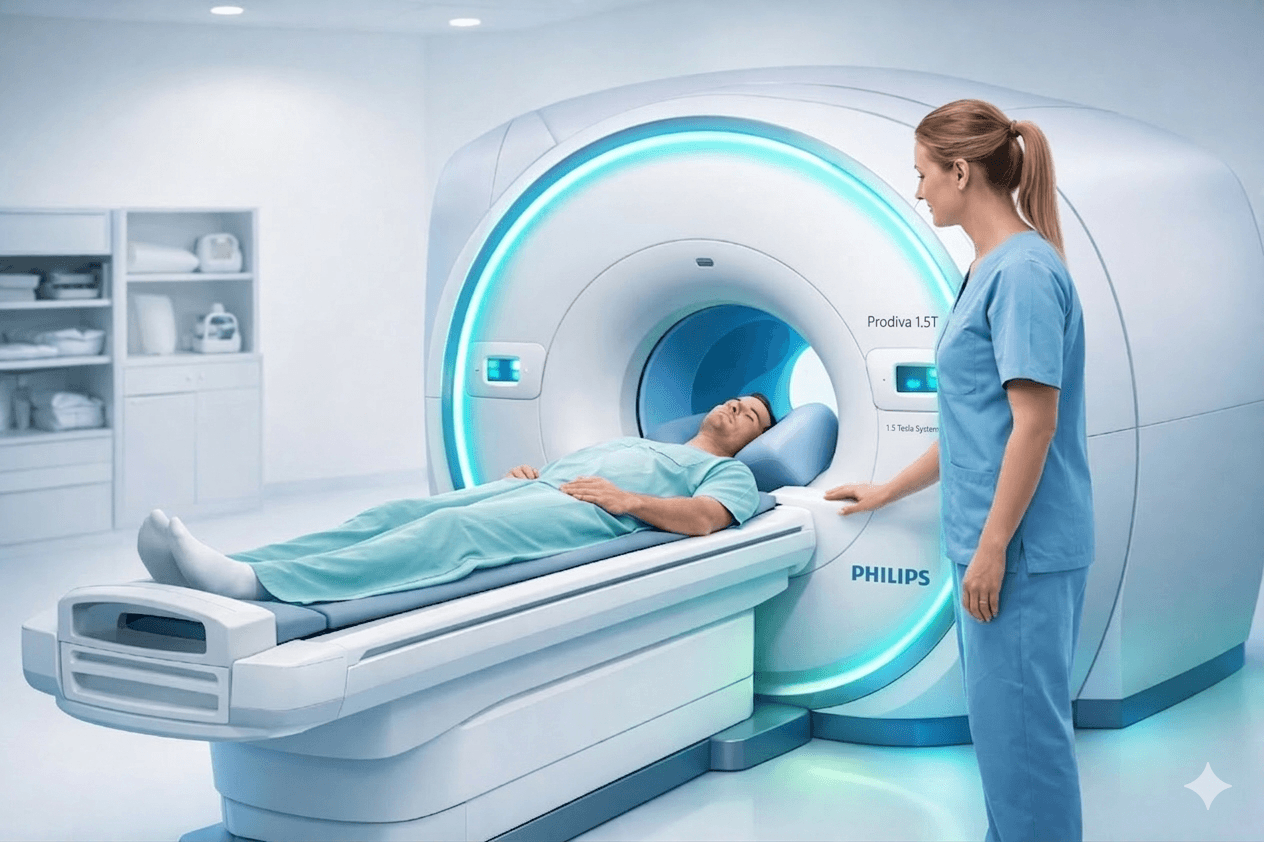

Resonancia Magnética

Equipo Philips Prodiva 1.5T. Diagnóstico de lesiones cerebro, tórax, columna, abdomen, próstata, tumores, huesos y articulaciones.

Philips Prodiva 1.5T

Tecnología de punta

Imágenes más detalladas y precisas con lo último en equipos médicos.